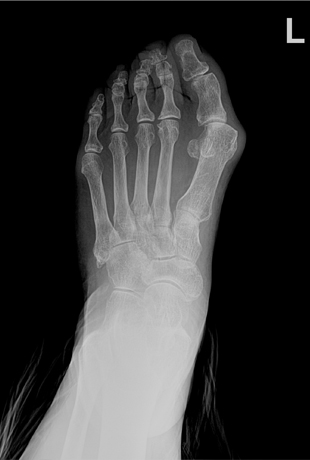

무지 외반증

무지외반증 수술 전